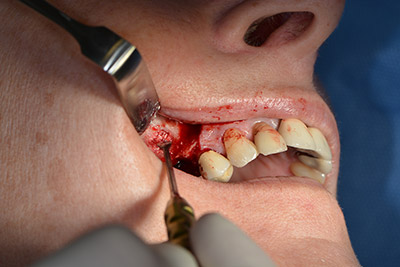

Surgical procedure for implantation

The classic incision (crestal, buccal relief) and the preparation of the mucoperiosteal flap enabled a good overview.

Sky implants (bredent) were used this case. The surgical protocol of these, specify pilot drilling at about 1200 rpm (Fig. 9).